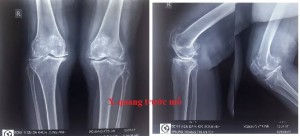

Tiếp tục phát triển về chuyên môn chấn thương chỉnh hình. Ngày 17/07/2017 Tại Bệnh viện Đa khoa Đông Anh, ca mổ thay khớp gối đầu tiên được thực hiện thành công bởi ekip do Thạc sĩ - bác sĩ Đoàn Anh Tuấn mổ chính; phụ mổ bác sĩ Ngô Văn Hải và bác sĩ Lê Hữu Quang; gây tê ngoài màng cứng: do bác sĩ Ngô Thị Thu Phương phụ tráchBệnh nhân là bà Hoàng Thị A 73 tuổi, được chẩn đoán thoái hóa khớp gối 2 bên. Đã được thay khớp gối phải toàn phần. Ca mổ được thực hiện trong 90 phút.